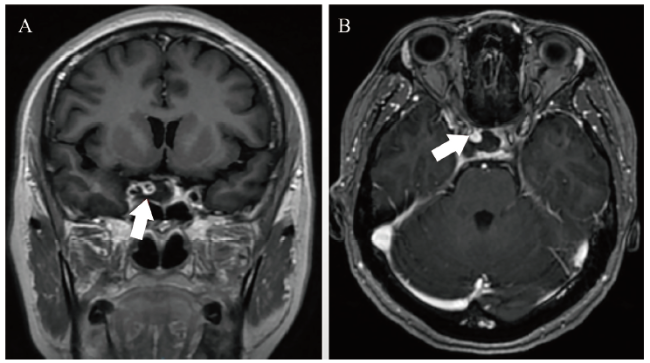

根据欧洲抗风湿病联盟/美国风湿病学会2019年发布的SLE分类标准,结合患者症状、体征、实验室检查结果,诊断为SLE、SLE血液系统损伤、狼疮肾炎、神经精神性SLE。SLEDAI-2000评分20分,治疗方案为口服甲泼尼龙40 mg/d,口服硫酸羟氯喹200 mg每日2次,考虑患者在外院使用过环磷酰胺且累积剂量达1.4 g,因此仅予0.6 g环磷酰胺静脉滴注诱导缓解治疗,同时予兰索拉唑、阿法骨化醇、碳酸钙D3支持治疗。1月22日晚患者开始出现头痛、呕吐及眼球向内、向上活动受限,予眼科会诊,完善光学相干断层成像(OCT)提示,双眼浆液性视网膜剥离,荧光素血管造影(FFA)提示右眼黄斑上方可见渗漏点。同时行头颅MRI示右侧海绵窦区见一结节状异常信号灶(图2),呈现不均匀性血管流空影,最大直径达23 mm,考虑患者颅内动脉瘤较大且已经压迫动眼神经引起相应症状,随时有破裂风险,经疑难病例讨论后,在积极规范治疗SLE的同时转神经外科进行手术治疗。

图2 一例SLE伴颅内动脉瘤致右眼睑下垂患者的头颅MRI结果

注:右侧海绵窦区见一结节状异常信号灶(箭头所示),其中A为头颅MRI冠状位影像,B为头颅MRI水平位影像。